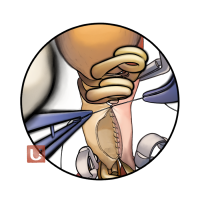

監修:谷川 緑野 / 札幌禎心会病院脳卒中センター

監修:太田 仲郎

監修:永田 雄一